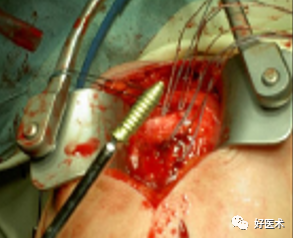

附:大结节撕脱骨折内固定

适用经手法复位失败,骨折移位超过1cm者;骨折块拉至肩峰下。

麻醉:颈丛麻醉 。

体位:仰卧位,患肩垫高与手术台成30°角。

操作方法:

切口:自肩峰外侧缘,约5cm,平行于三角纤维方向。

劈开三角肌纤维,切开三角肌肩峰和锁骨外侧端的附着点,显露结节部

在结节上用3.0钻头朝肱骨头方向钻孔,深约12-20mm

用钛丝穿过肩袖

将钛丝缠绕螺钉钉帽一圈

选择合适长度螺钉

拧入干预螺钉至钉帽外露3mm深度

用钢丝钳把钛丝缠绕拧紧,检查骨折复位情况

冲洗伤口,逐层缝合肌肉,皮肤切口

曲肘90°位三角巾悬吊制动,2周后开始被动活动